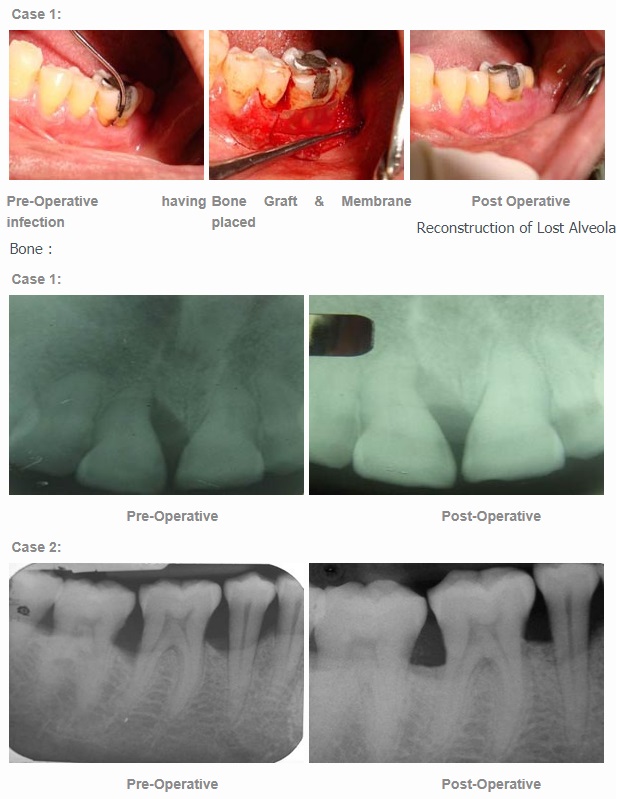

Grafting is the replacement or augmentation of the bone around the teeth. It is performed to reverse the bone loss / destruction caused by periodontal disease, trauma, or ill fitting removable dentures. It is also used to augment bone to permit implant placement, such as augmenting bone in the sinus area for implant placement, or augmenting bone to enhance the fit and comfort of removable prostheses, or to enhance esthetics of a missing tooth site in the smile zone. When one loses a tooth, as in an extraction, the surrounding bone collapses. To preserve this bone for future implant placement or for esthetics, a bone graft is used.

Bone Gum Placement:

Guided Tissue Regeneration